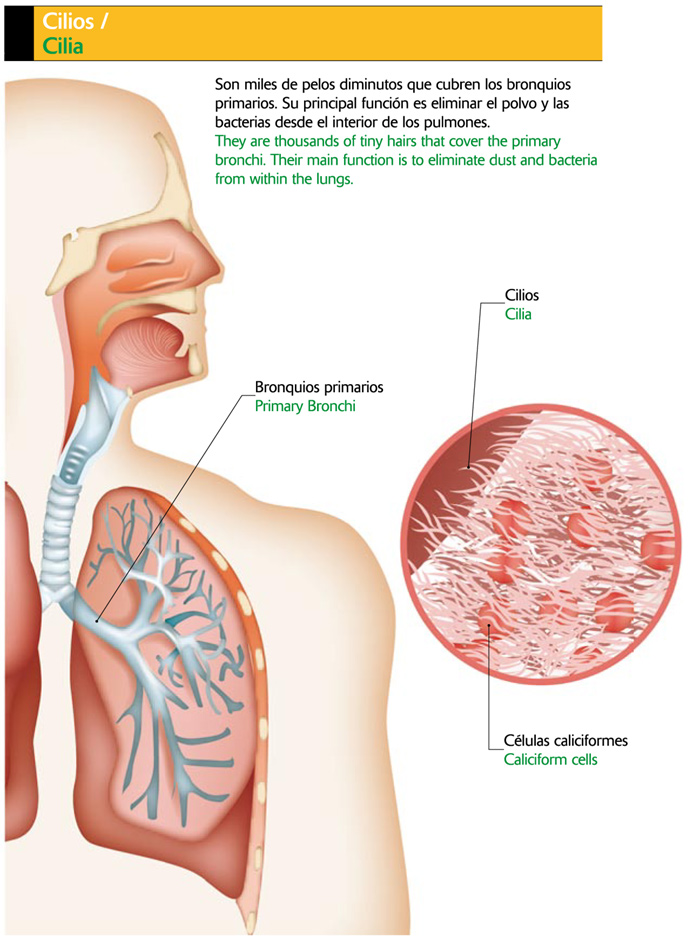

Bronquios: Al final del trayecto, la tráquea se bifurca dando origen a los Bronquios derecho e izquierdo. La estructura de los bronquios es similar a la tráquea, es decir, poseen anillos cartilaginosos incompletos, revestidos internamente con mucosa ciliada.

Cada bronquio penetra en el pulmón a través de su borde interno (del pulmón) y por donde entran también, vasos arteriales, venosos y linfáticos.

El Pulmón derecho presenta tres lóbulos y el izquierdo dos. Así, el Bronquio derecho se divide en 3 ramas principales, una para cada lóbulo antes de seguir subdividiéndose; mientras que el bronquio izquierdo se divide en dos ramas principales. Cuando los Bronquios más pequeños llegan a tener menos de 1 mm de diámetro, el cartílago desaparece y pasan a llamarse Bronquiolos, cuyas paredes están constituidas por músculos. Cada Bronquiolo al dividirse origina los conductos alveolares, los que a su vez desembocan en los Sacos Alveolares o Alveolos (Ver figura 4).